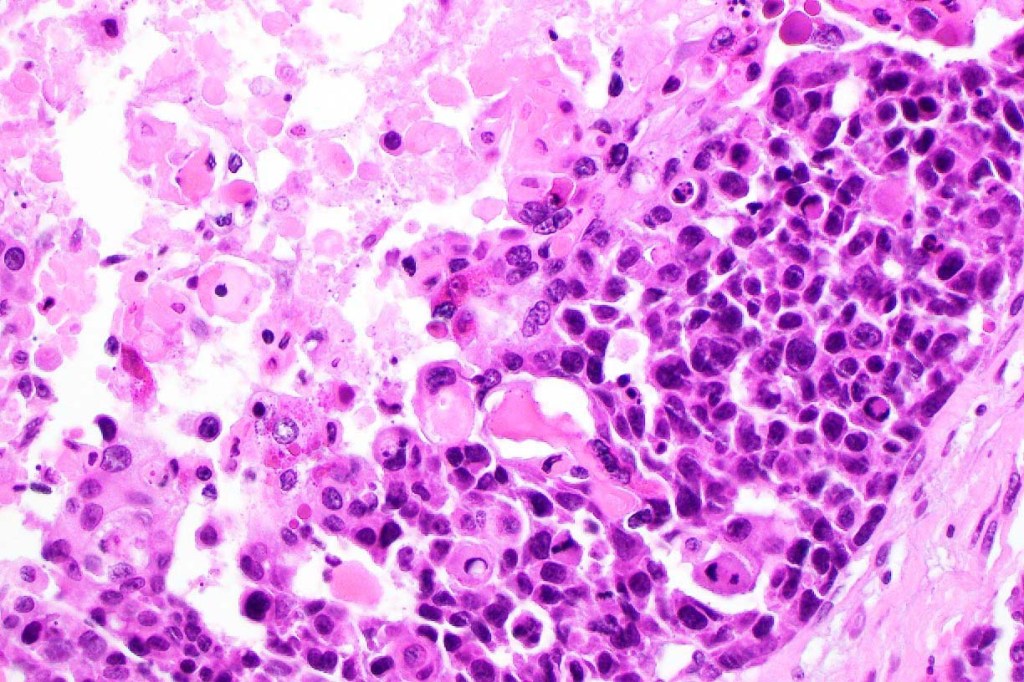

•Lobular or a diffusely infiltrating growth pattern. Composed of pleomorphic hyperchromatic, basaloid cells with nucleolar prominence, abundant mitoses & atypical mitoses (brisk mitotic activity should not be used as a defining feature of matrical carcinoma since in the evolving phase mitoses are typically very numerous in pilomatricoma)

•Necrosis common

•Clear cell change